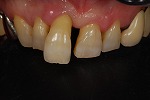

~術前~

オールセラミック修復

~術後~